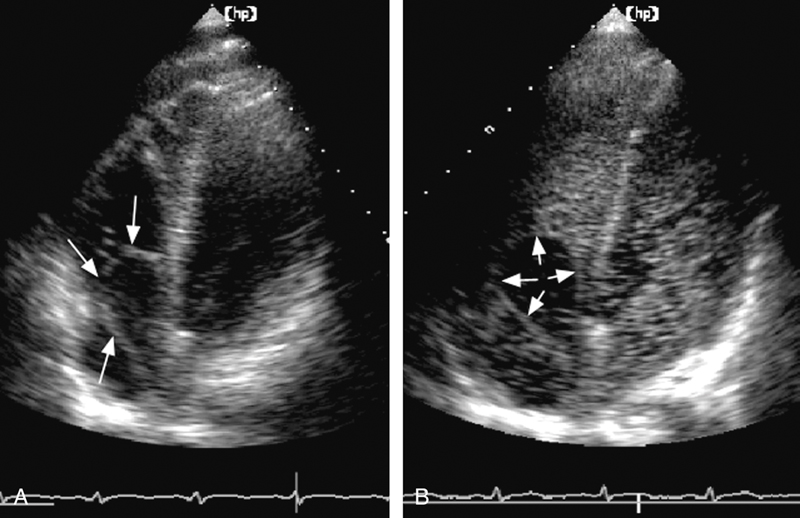

فحوصات تشخيصية لبعض امراض القلب والشرايين التاجية